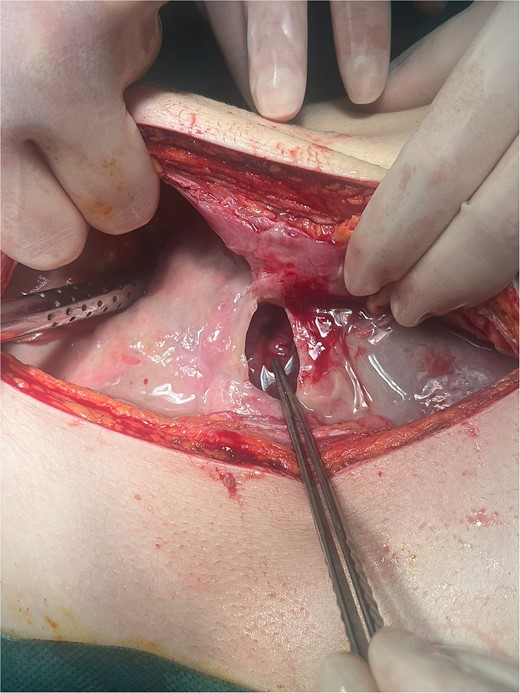

Intraoperatively, a giant ulcer in the antropyloric region of the stomach adhered to the round ligament was noted (Fig. 2), accompanied by diffuse fibrinous peritonitis. The ulcer was detached from the anterior abdominal wall, and the diameter was measured to be 4 × 3.5 cm (Fig. 3). A biopsy of the ulcer was taken. A thorough intraabdominal lavage with warm saline was conducted. The ulcer was treated with omental patch ulcer closure according to Cellan–Jones [7] by the use of six slowly absorbable sutures. Two intraabdominal drains were placed in the Morisons’s space and Douglas’s pouch, respectively.

Giant ulcer of the anterior wall of the stomach adhered to the round ligament (intraoperative finding during laparotomy).